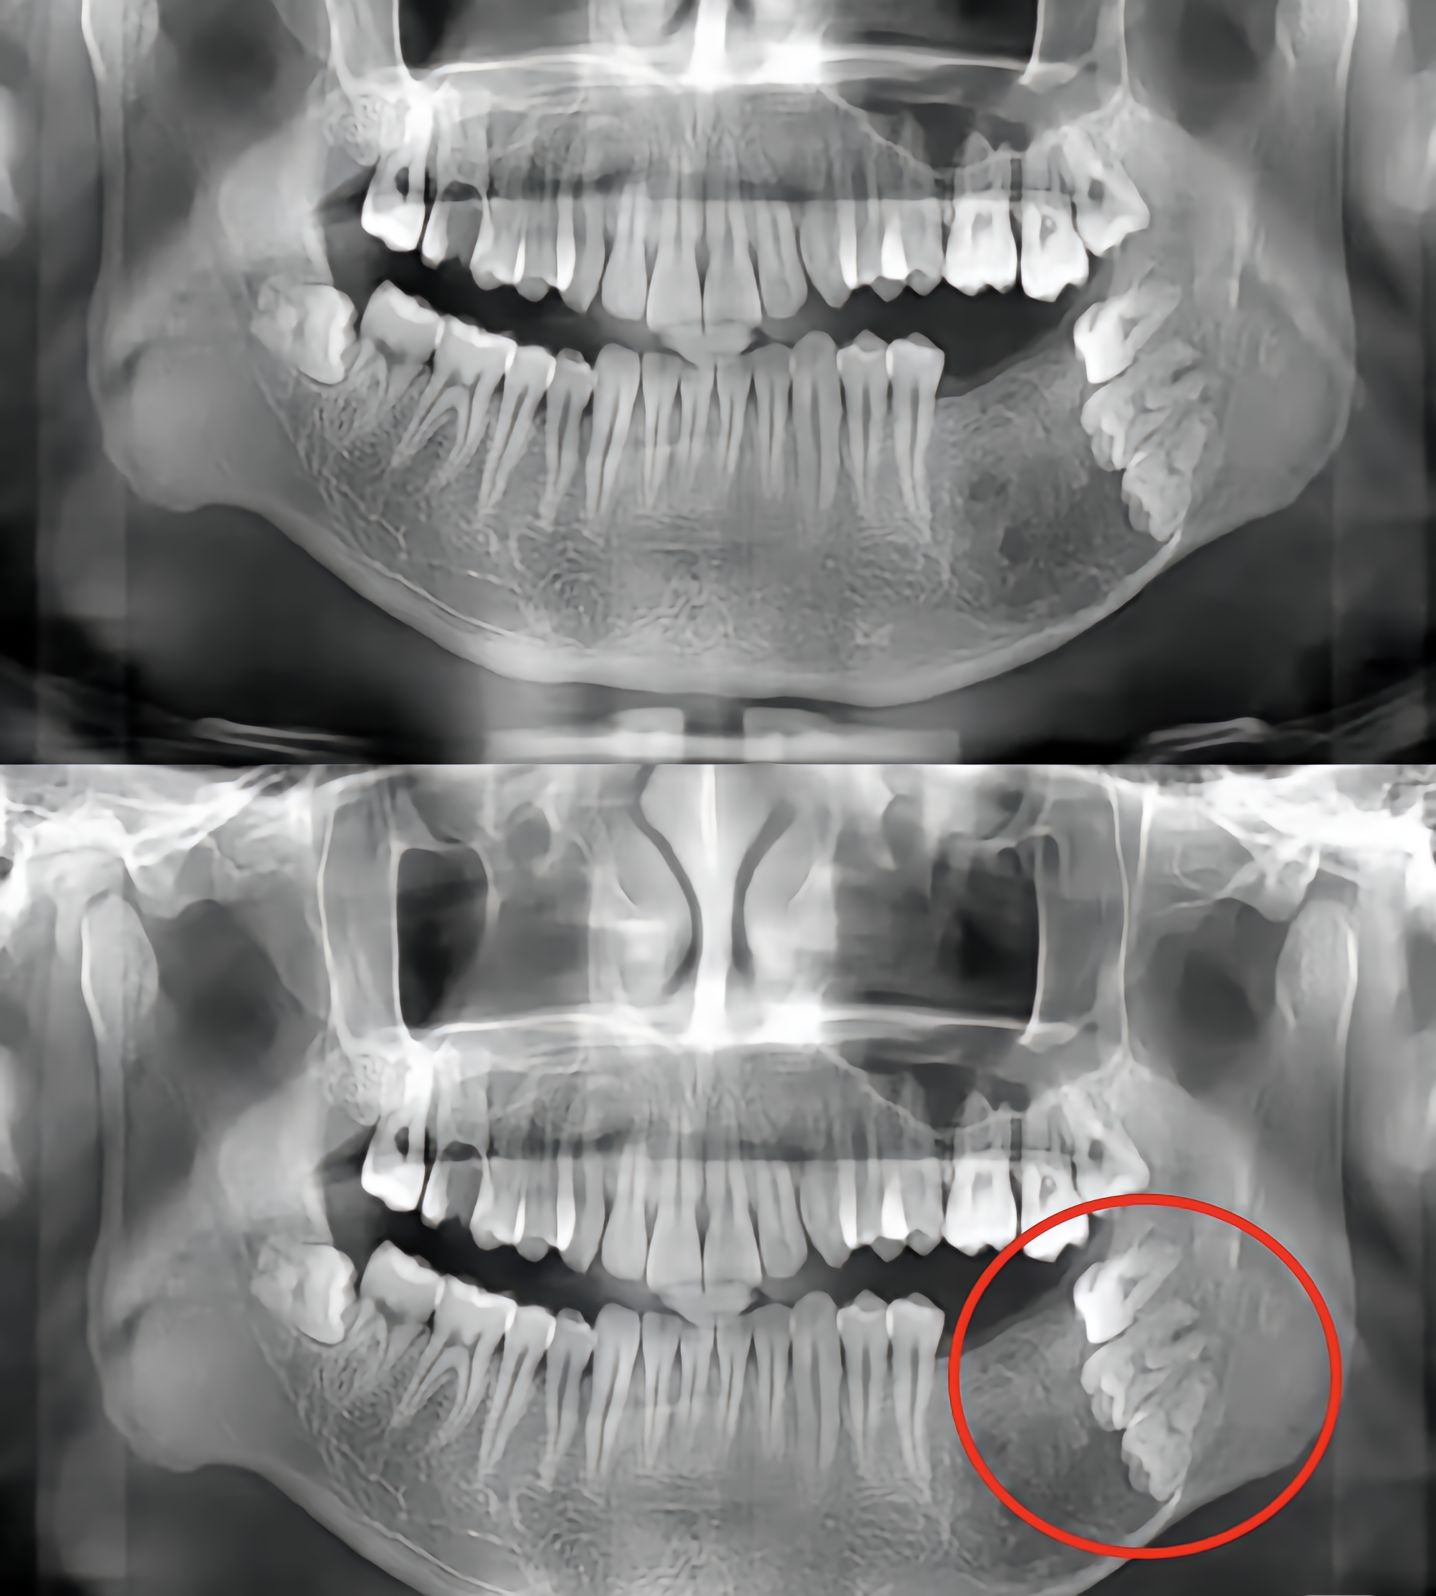

不按套路生长的牙齿

不按套路出牌了